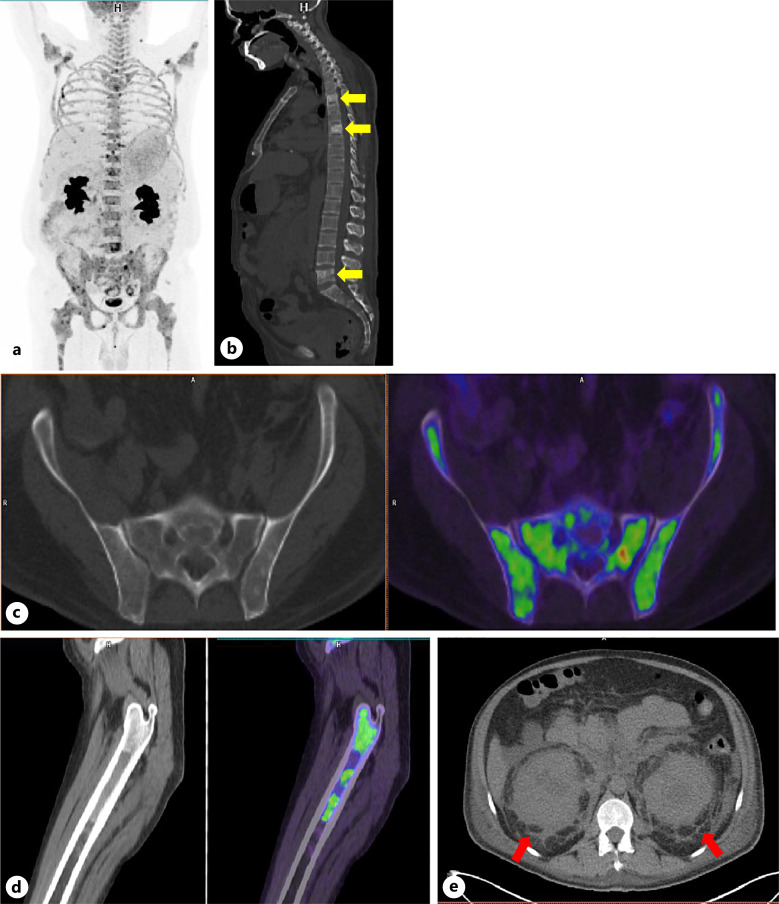

Case presentation: We present a 45-year-old male with nonspecific clinical symptoms and progressive skin and abdominal lesions. Multiple tissue biopsies revealed fibrohistiocytic infiltration but provided an inconclusive diagnosis. Imaging studies showed extensive fibrosis in the perinephric regions on CT and sclerotic foci in long and pelvic bones on PET/CT. Bone marrow biopsy revealed abnormal histiocytes with multinucleated giant forms, prominent emperipolesis, active hemophagocytosis, and condensed hemosiderin deposition. Immunohistochemistry showed positive histiocytes for CD68, CD163, and partially for S-100. Molecular analysis confirmed the BRAFV660E mutation, establishing a diagnosis of ECD with atypical histologic features and findings overlapping with Rosai-Dorfman (mixed histiocytosis). The diagnosis was challenging due to extensive fibrosis, the lack of typical histopathologic features of ECD, in addition to concurrent involvement by Rosai-Dorfman cells (mixed histiocytosis), activated macrophages, and dense hemosiderin deposition - a morphologic characteristic not previously described in ECD. Unfortunately, the diagnosis was delayed by 6 years, which tragically led to a fatal outcome.